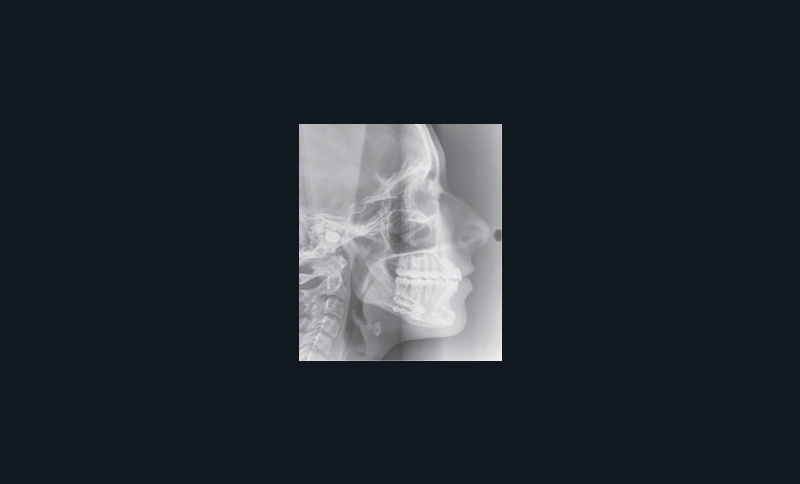

Son visage de face est équilibré et symétrique ; en revanche, au niveau de son profil elle présente une rétromandibulie avec un sillon labio-mentonnier marqué.

Sur le plan dentaire, elle présente une classe II d’Angle complète, une supraclusion de 4 mm et un surplomb de 6 mm ne correspondant pas au décalage de classe II molaire.

À la vue de l’examen radiographique, elle est au stade CS6 d’après la méthode de maturation vertébrale de Baccetti [1]. Elle présente une classe II squelettique de Ballard par rétrognathie mandibulaire avec un ANB de 9° et un AoBo de 9 mm sur un schéma facial normo-divergent. L’incisive mandibulaire est vestibulo-versée (IMPA = 114°). Le maxillaire est bien positionné. Elle présente de plus une dysharmonie dento-dentaire (DDD) antérieure par excès mandibulaire.